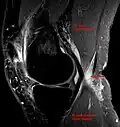

Die Diagnose wird neben der klinisch-manuellen Untersuchung durch Ultraschall (Sonographie) und evtl. eine Kernspintomographie erhärtet; dabei werden auch Differentialdiagnosen wie Aneurysmen der Popliteal-Arterie oder -vene[3] ausgeschlossen.